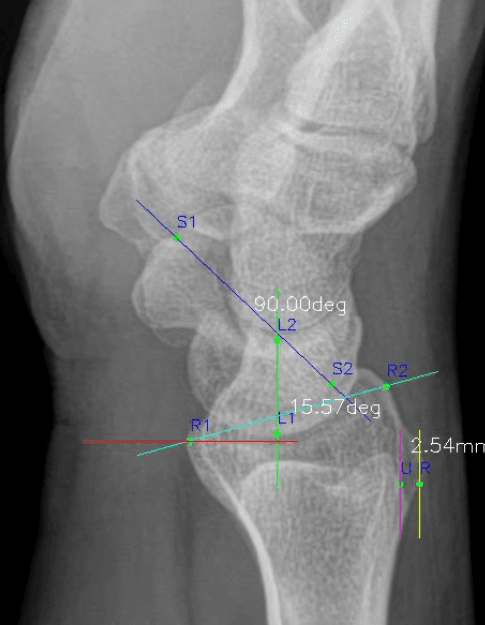

WALK101, Wrist_Lat_AIX 출시… 손목 X-ray(LAT) 자동 측정으로 임상 파이프라인 확장

Wrist_Lat_AIX는 손목 Lateral X-ray에서 주요 불안정 진단 관련 지표를 자동 측정하는 AI 솔루션으로, MFDS 1등급 의료기기 인증을 획득했습니다.